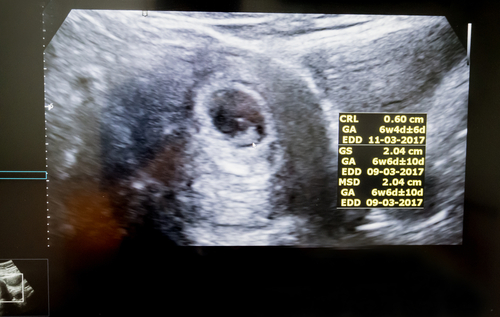

妊娠6週の胎芽の状態

胎芽である赤ちゃんが、だんだん細長い形に成長してきます。目や口、手、足のもとが作られてきます。妊娠6週頃に入ると心拍が確認できる人も出てきますが、妊娠7週以降に確認できる場合も多いです。心拍が確認できないと不安になるかもしれませんが、出血や強い腹痛など不安な症状がない場合は、焦らず次の妊婦健診を待つようにしましょう。